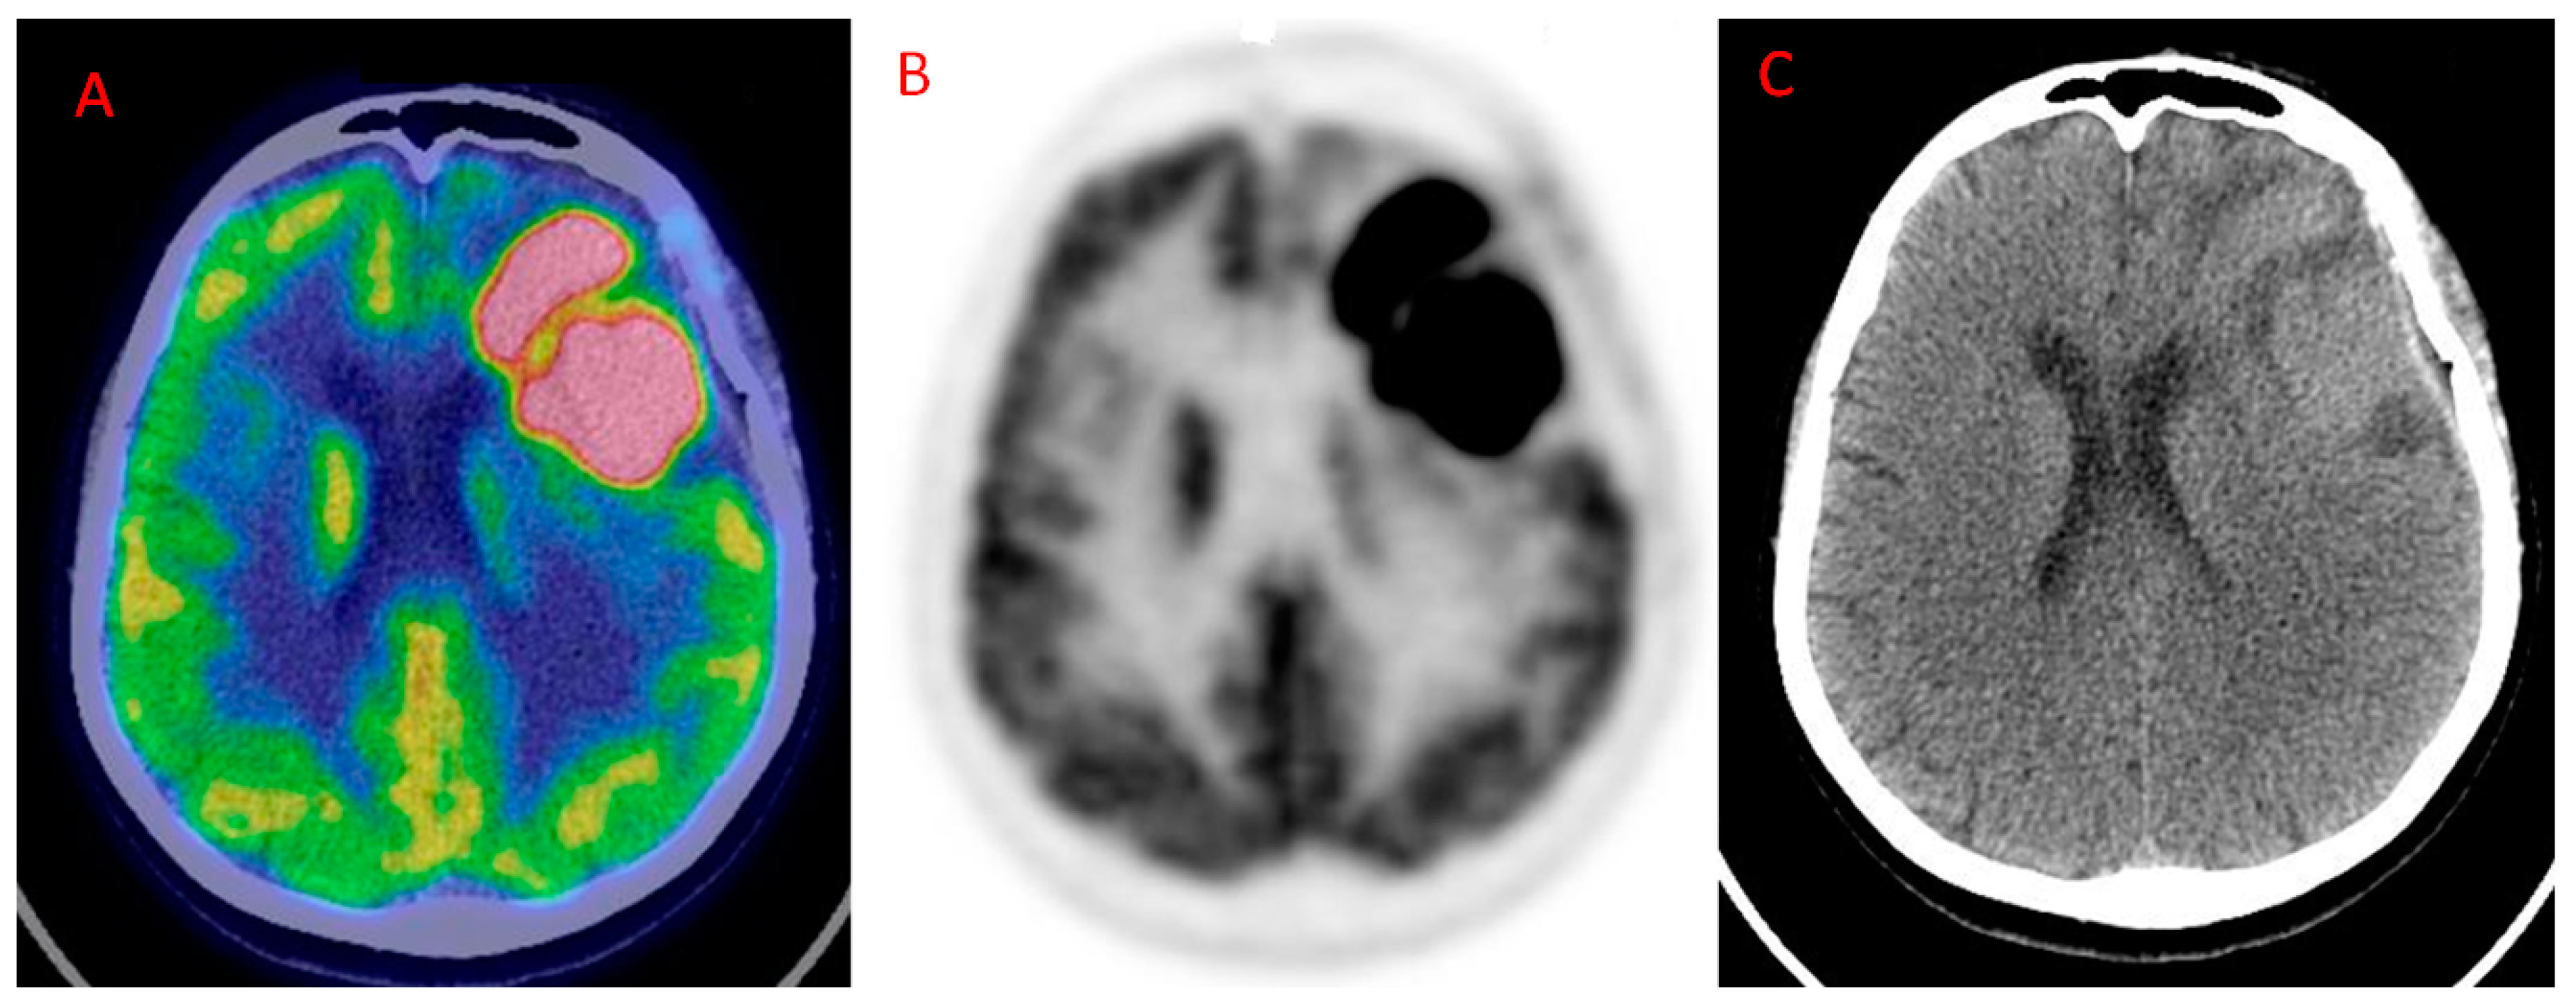

| Idegushi et al. [34] | 2018 | P | 16 | II = 8 III = 8 | PET/CT | Gd MRI, T2-w, FLAIR | 18F-FDG PET may also help in planning surgical resection. Only partial overlap between 18F-FDG uptake and the contrast-enhancement area. Tissue extracted from the 18F-FDG and Gd MRI positive areas presented anaplastic features. Tissue extracted from 18F-FDG and Gd MRI negative areas resulted in grade II glioma at pathological examination. |